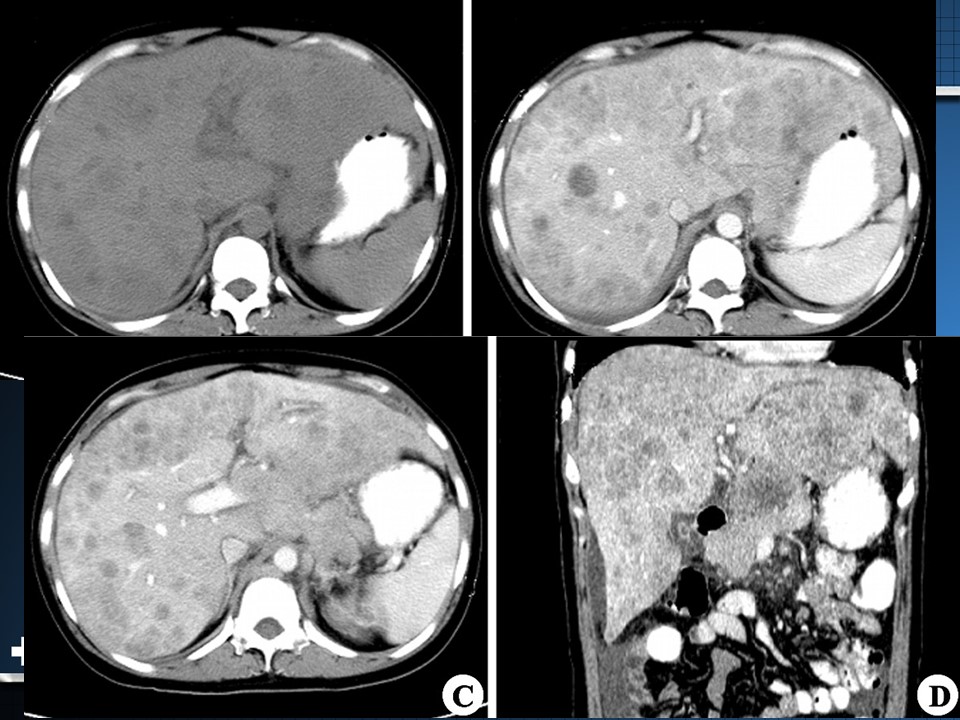

“原发性肝癌PPT” 的相关文章